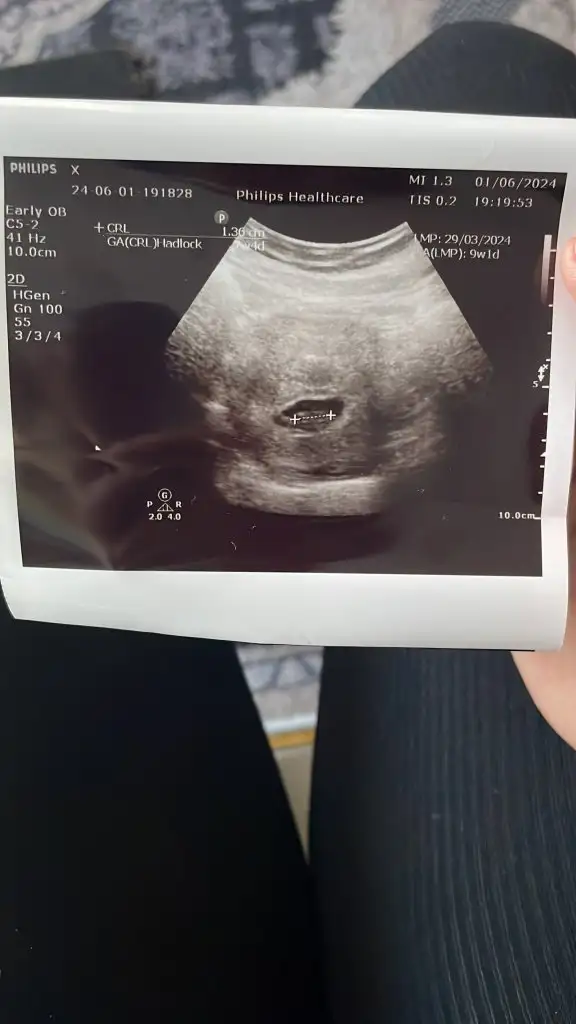

10+3 haftalık vajinal ultrason. Tahmininizi söylerseniz sevinirim 🌸

Eklentiler

• IMG_4793.webp

IMG_4793.webp

57,8 KB · Görüntüleme: 69